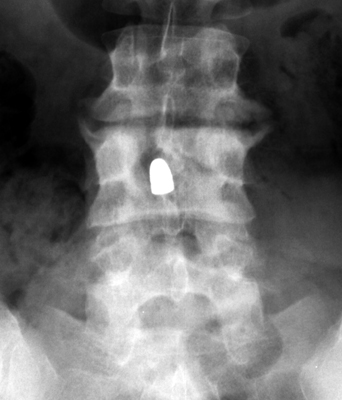

Tumbling Bullet Sign

Two sets of frontal and lateral radiographs, separated only by time, which reveal the "tumbling bullet sign"--which is simply a bullet which changes its location and orientation within a solitary bone cyst. This sign serves two purposes. It is documentation of the evolution of a solitary bone cyst as a corollary of trauma, and reveals the free movement of the foreign body within the confines of the lesion establishing its cystic rather than solid nature. It is similar to the fallen fragment sign.

- Click on the image for a larger versionA - Click on the image for a larger versionB - Click on the image for a larger versionC - Click on the image for a larger versionD